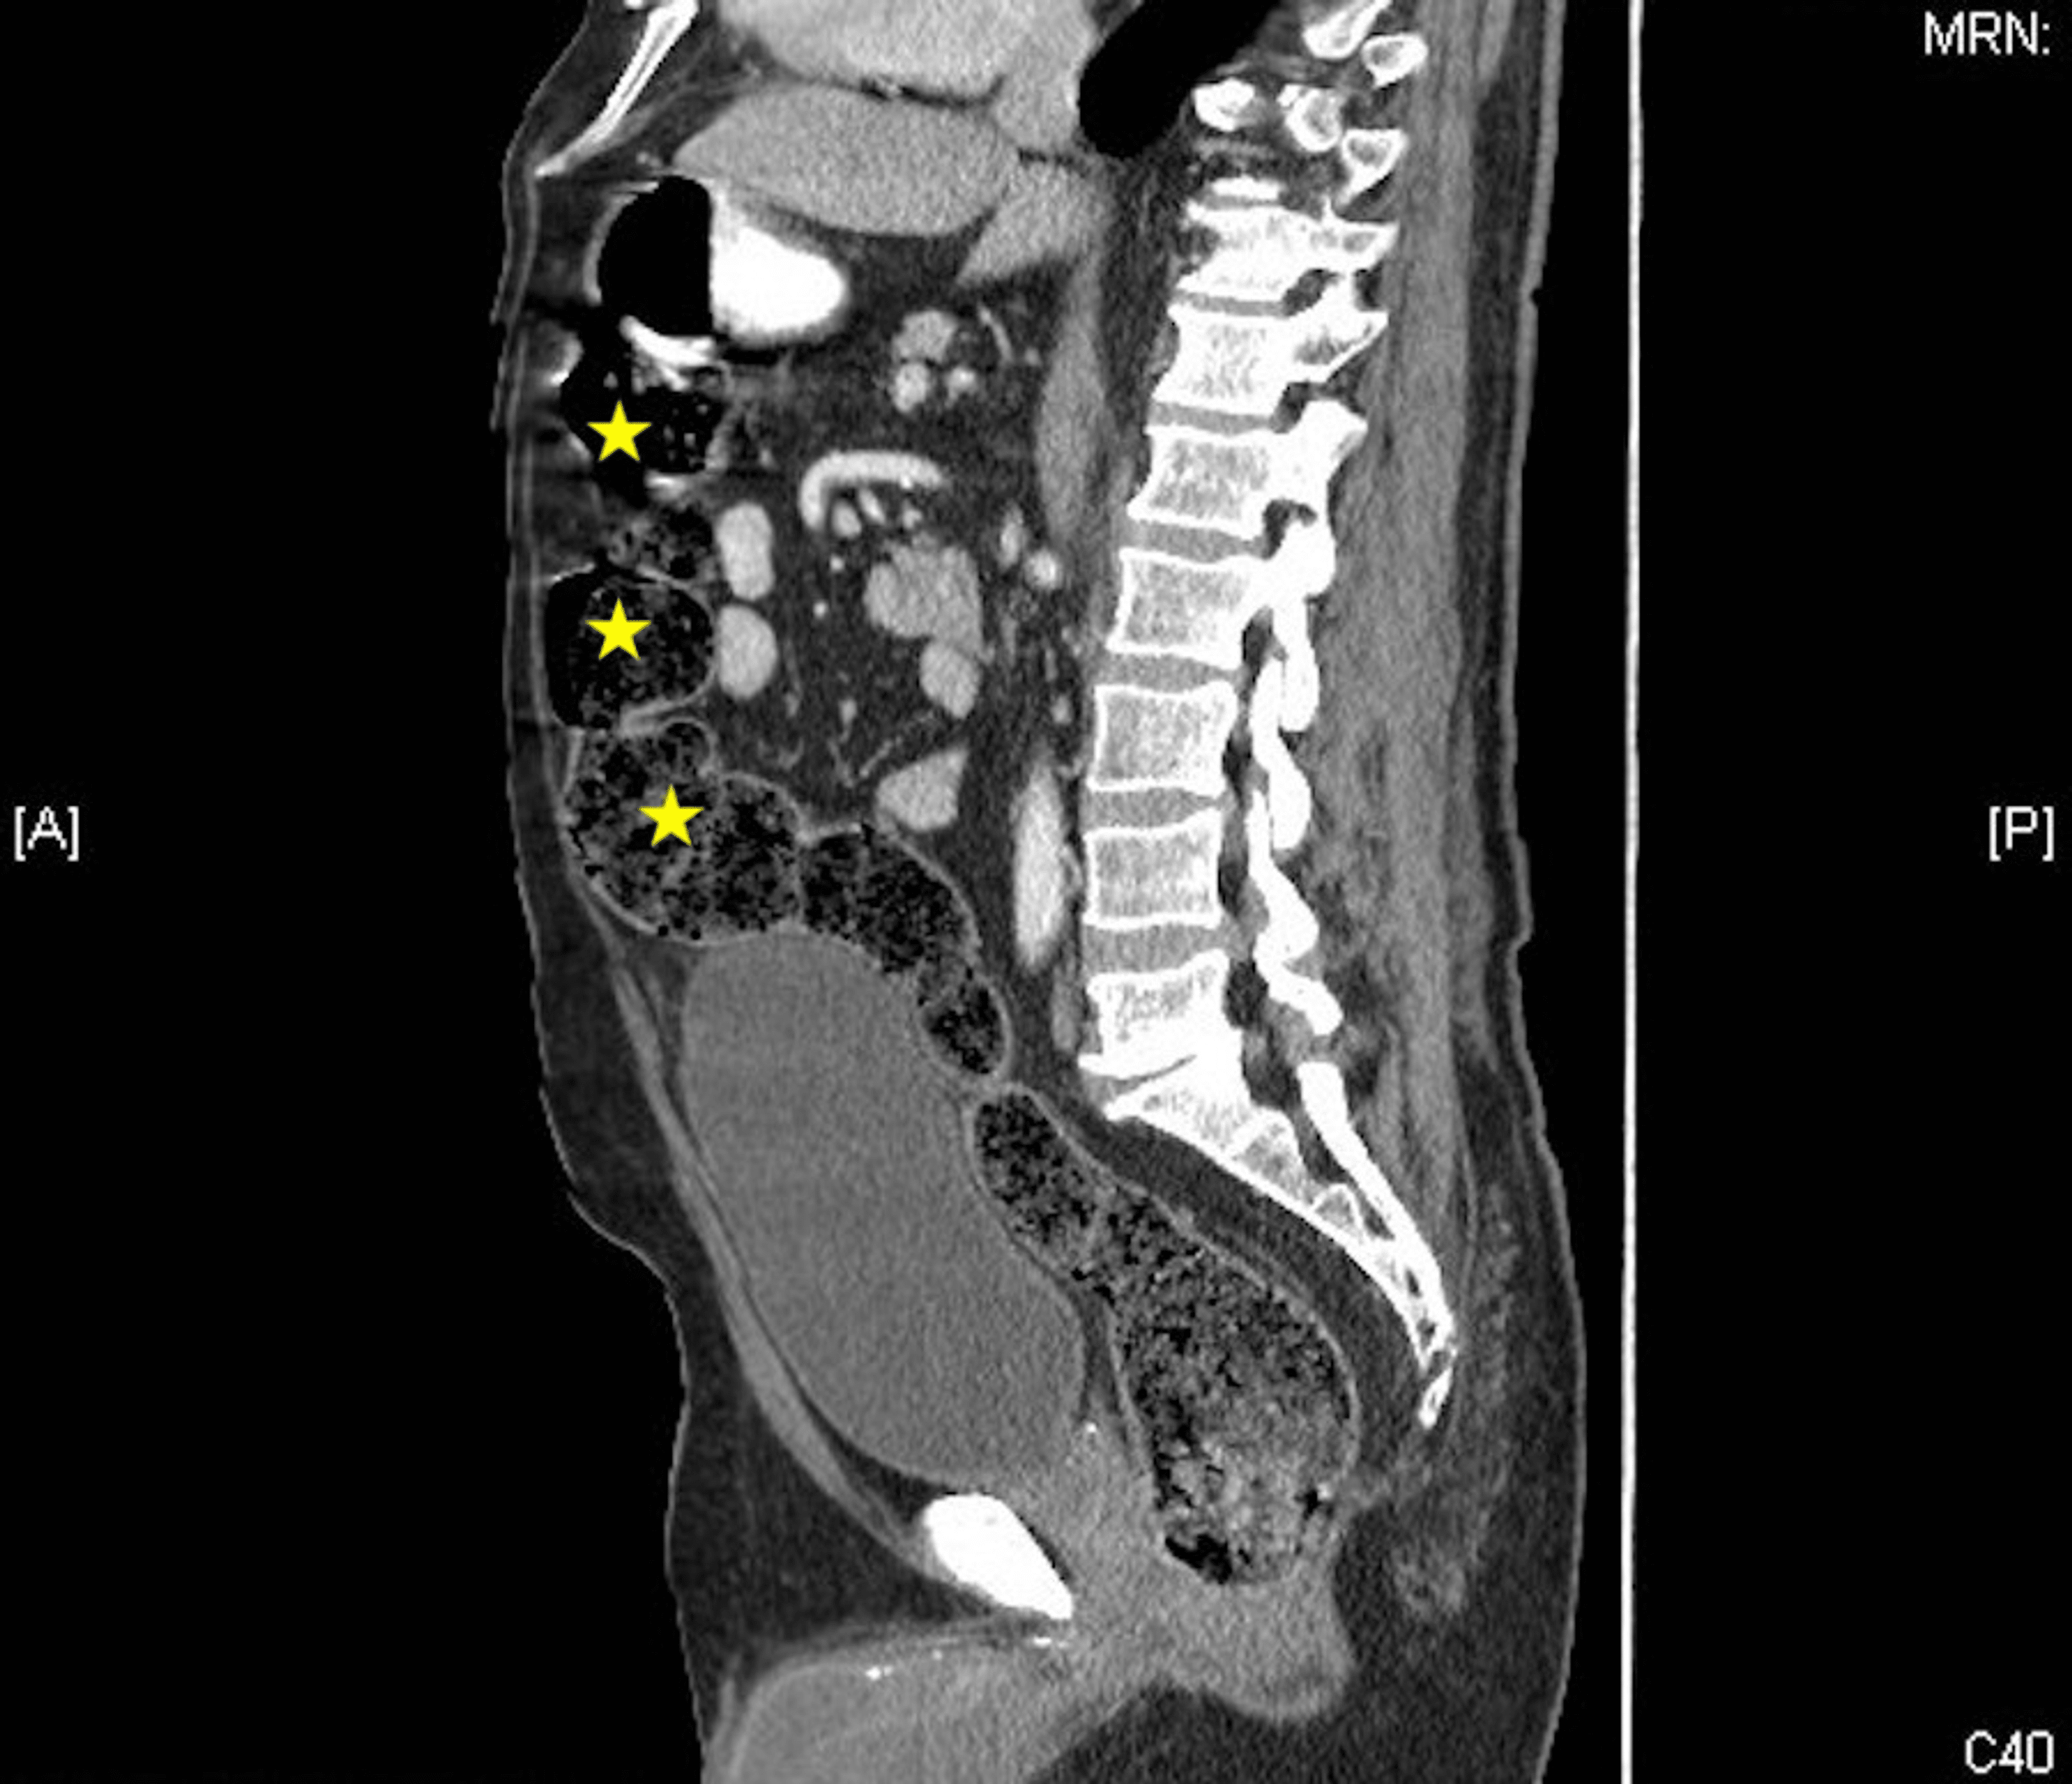

From www.svuhradiology.ie

Acute diverticulitis CT Radiology at St. Vincent's University Hospital Flaxseed Diverticulitis Diverticulitis (also referred to as a. learn more about the best diet for diverticulitis, including the role of fibre and supplements, as well as what to do if you’re in a. diverticulitis is a condition in which the diverticula, small, bulging pouches or sacs that grow inside the walls of your colon (large intestine), get inflamed or infected.. Flaxseed Diverticulitis.

From www.cureus.com

Cureus RightSided Diverticulitis A Rare Cause of RightSided Flaxseed Diverticulitis Having had an episode of diverticulitis in the past. it occurs when small pouches form in your intestine and push outward, like tiny balloons, at weak spots in your colon. discover if chia and flax seeds are beneficial for diverticulitis, and learn about common misconceptions regarding. diverticulitis is a condition in which the diverticula, small, bulging pouches. Flaxseed Diverticulitis.

Cureus Cecal Diverticulitis in a Geriatric Patient Flaxseed Diverticulitis diverticulitis is a condition in which the diverticula, small, bulging pouches or sacs that grow inside the walls of your colon (large intestine), get inflamed or infected. discover if chia and flax seeds are beneficial for diverticulitis, and learn about common misconceptions regarding. learn more about the best diet for diverticulitis, including the role of fibre and. Flaxseed Diverticulitis.